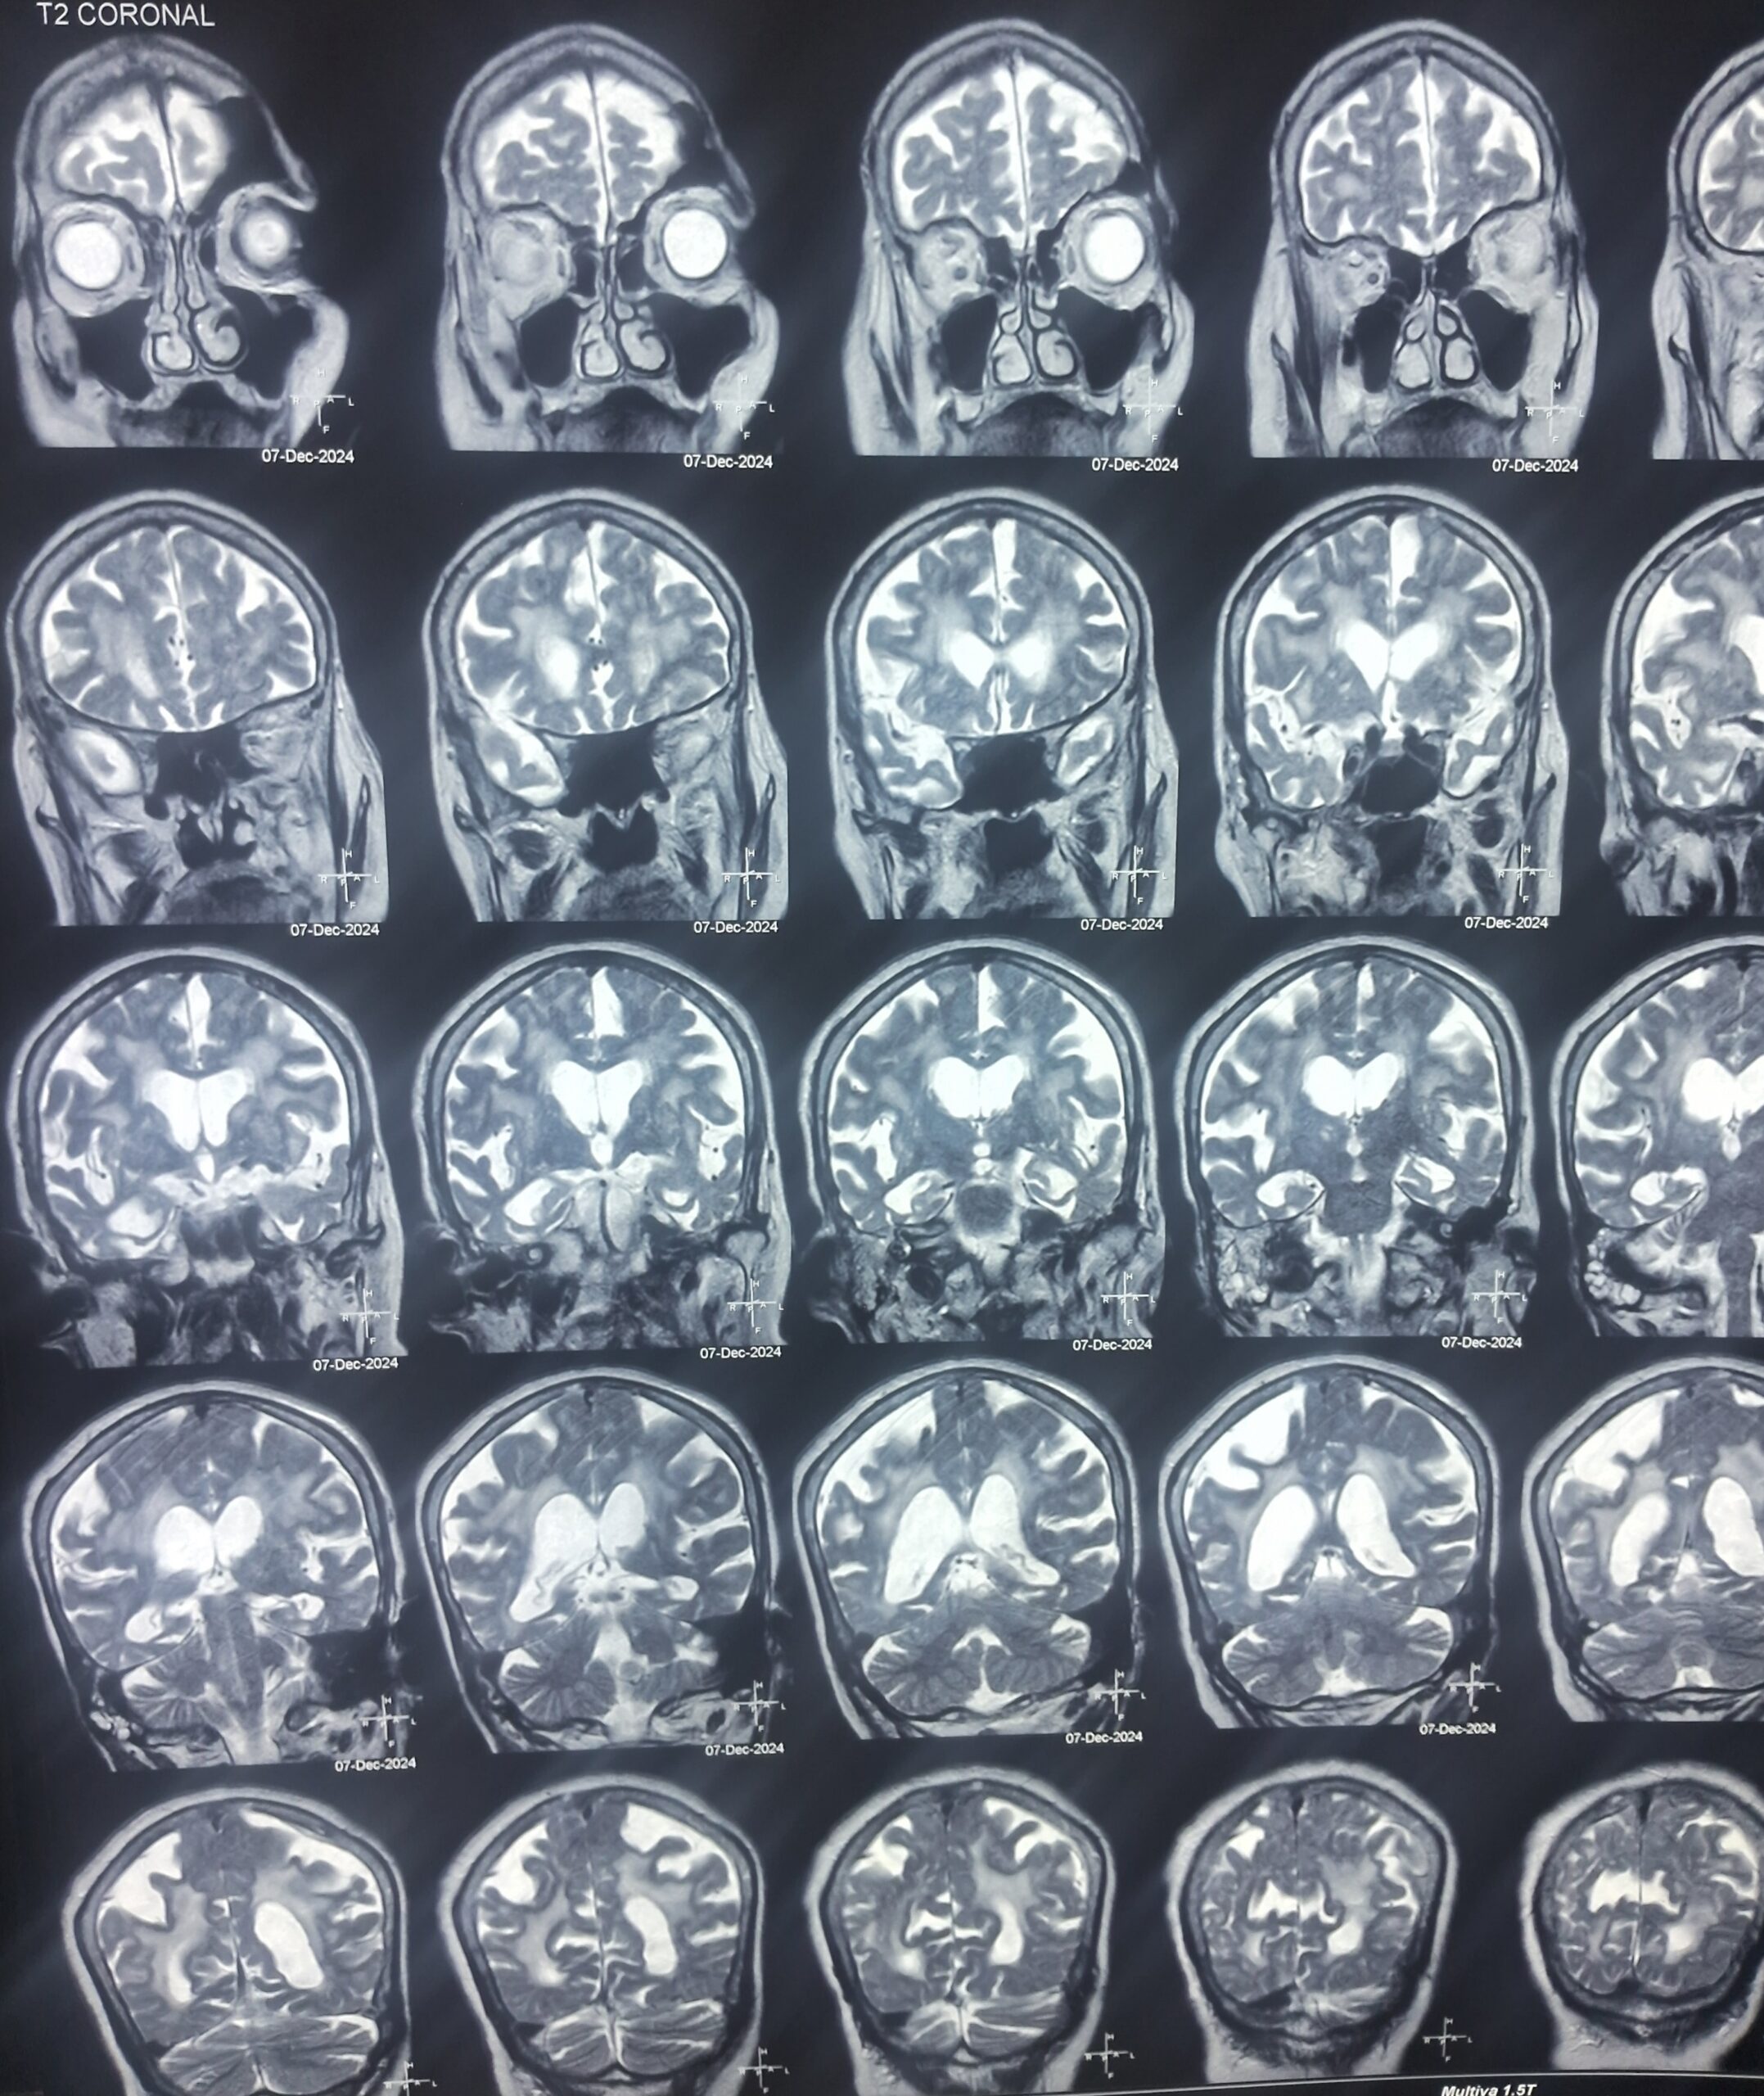

💡 Why a Specialist’s Cognitive Assessment is Essential ? More Than Just a Scan !!

When memory issues arise, structural assessments like MRI or CT scans are crucial to rule out reversible causes (e.g., vitamin deficiency, tumors, or vascular blocks like strokes), However, diagnosing Dementia requires a deeper, functional assessment.